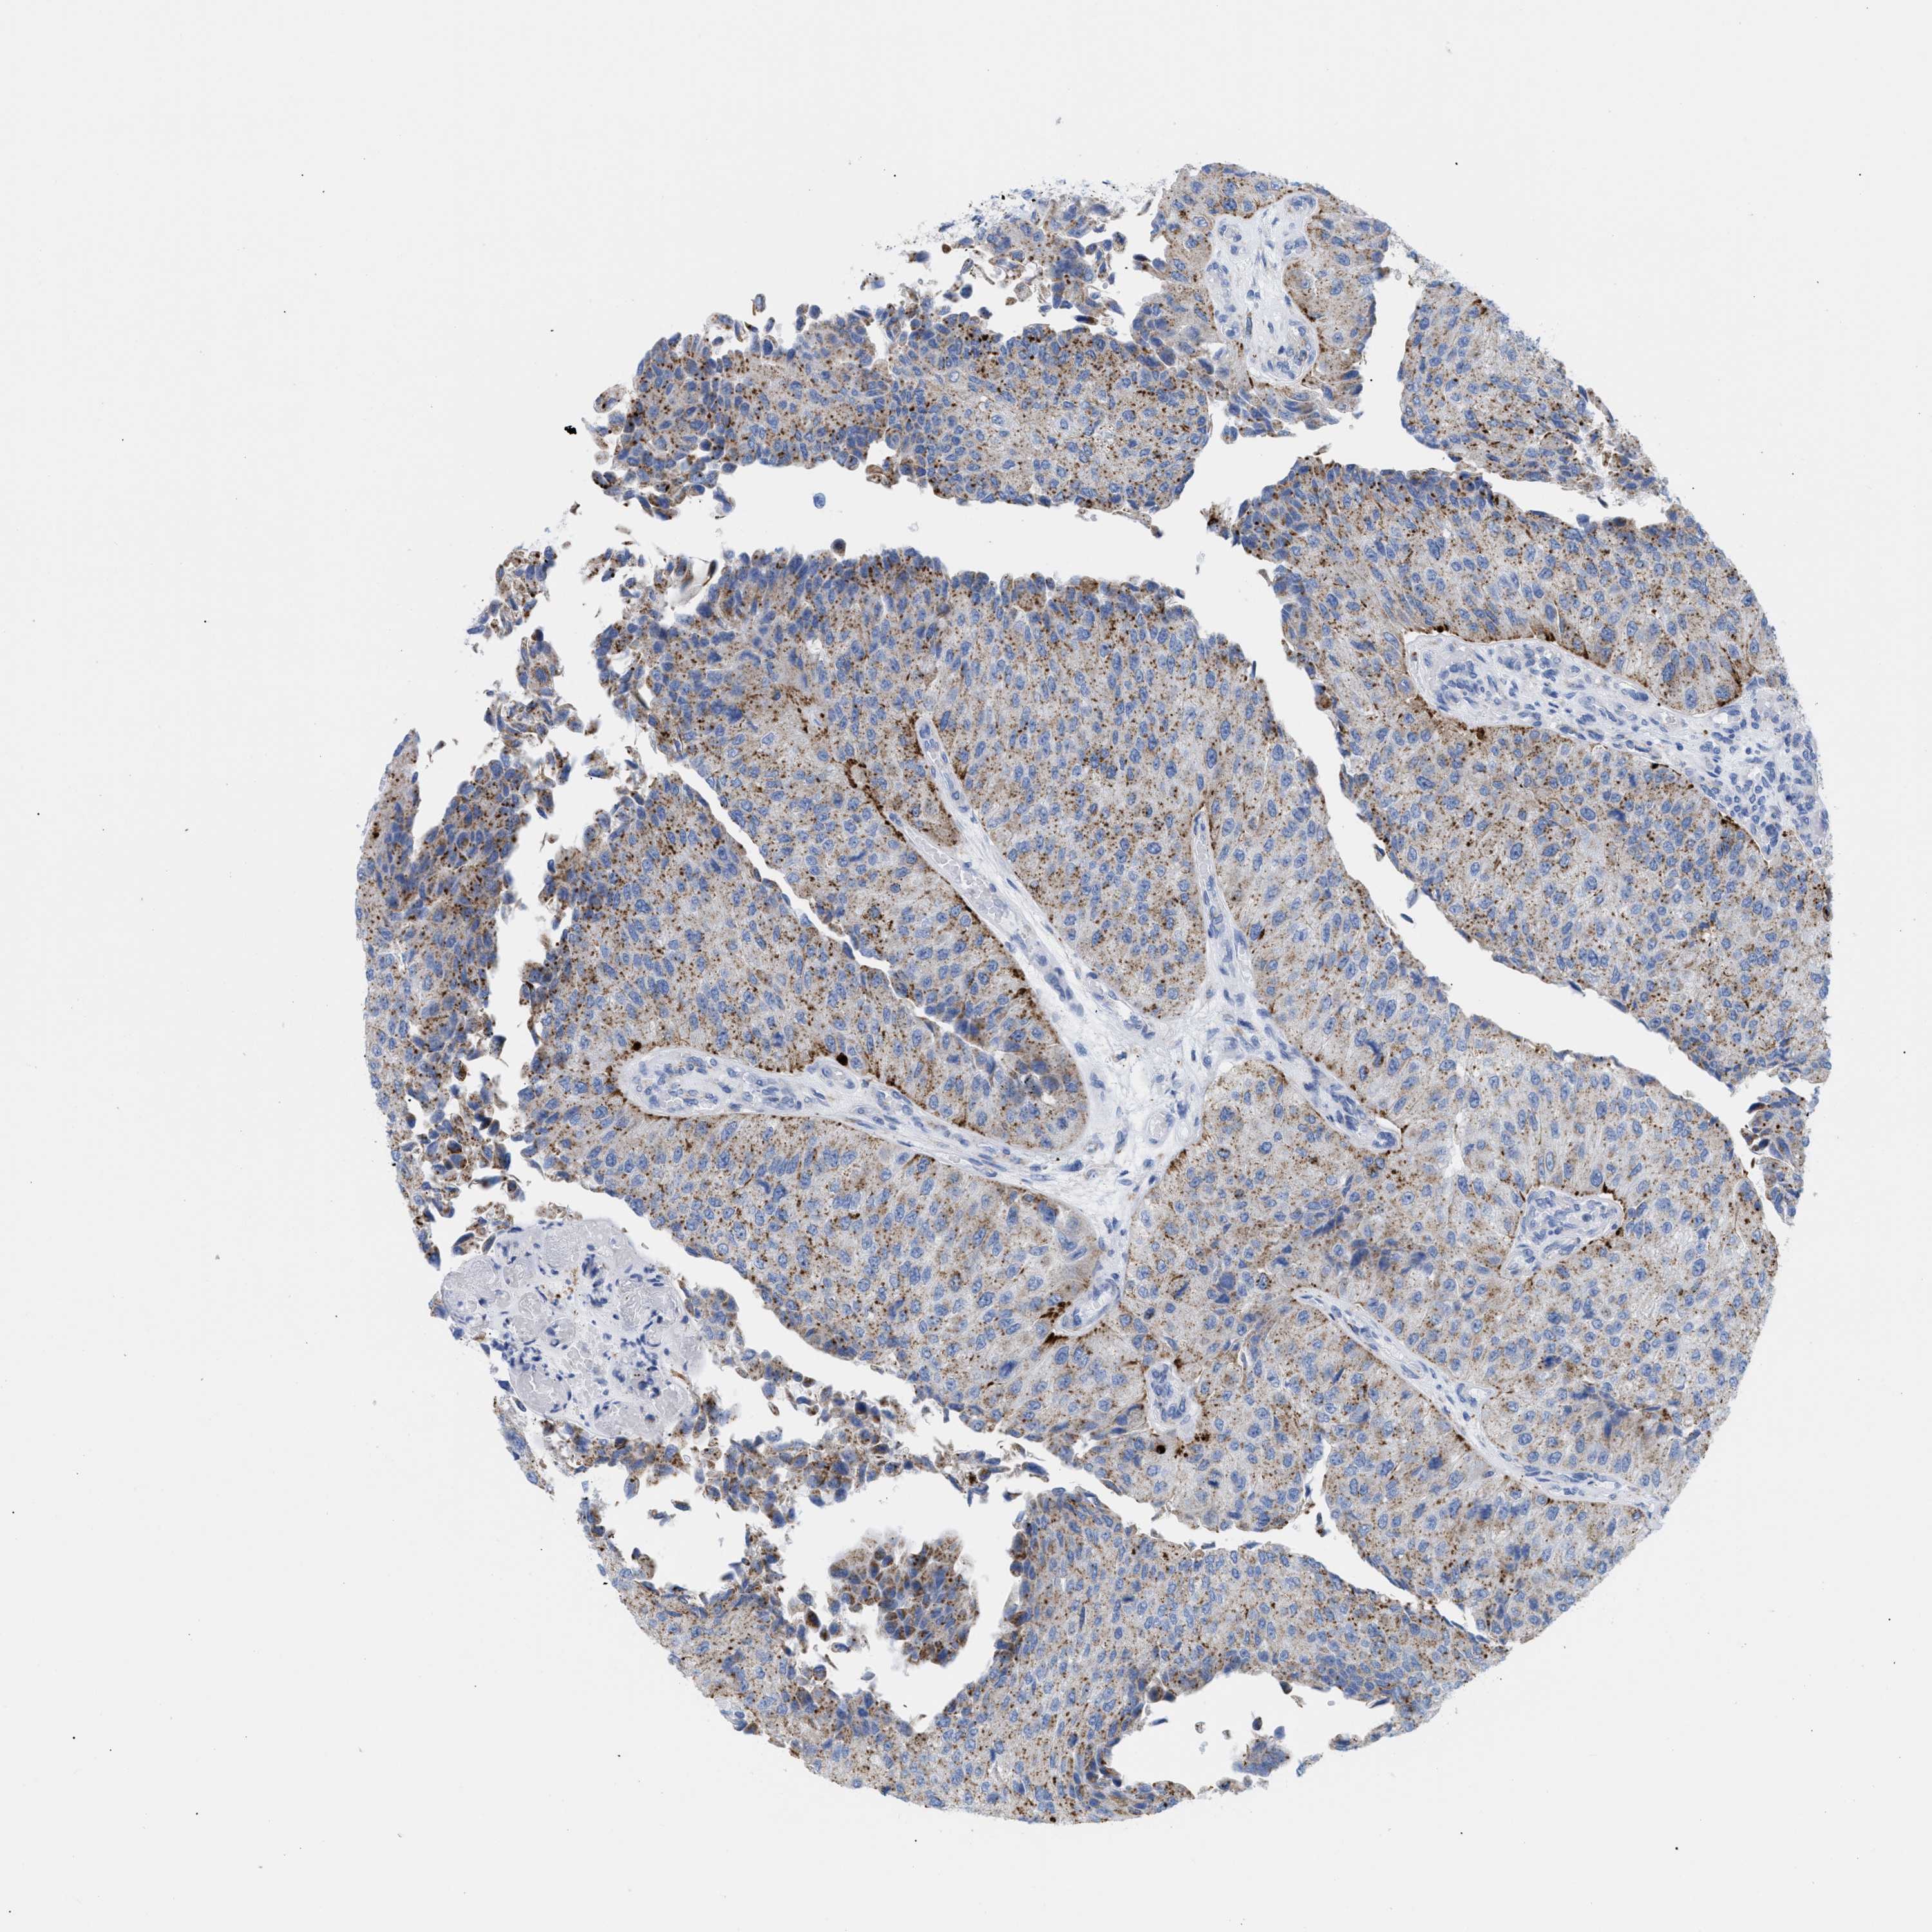

UROTHELIAL CANCER - Protein expressioni

A mouse-over function shows sample information and annotation data. Click on an image to view it in a full screen mode. Samples can be filtered based on level of antibody staining by selecting one or several of the following categories: high, medium, low and not detected. The assay and annotation is described here.

Antibody stainingi

Antibody staining in the annotated cell types in the current human tissue is reported as not detected, low, medium, or high, based on conventional immunohistochemistry profiling in selected tissues. This score is based on the combination of the staining intensity and fraction of stained cells.

Each image is clickable and will lead to virtual microscopy that enables deeper exploration of all samples and also displays staining intensity scores, fraction scores and subcellular localization as well as patient and tissue information for each sample.

Antibody HPA018036

Antibody HPA061701

Staining

High

Medium

Low

Not detected

Intensity

Strong

Moderate

Weak

Negative

Quantity

>75%

75%-25%

<25%

None

Location

Nuclear

Cytoplasmic/membranous

Cytoplasmic/membranous,nuclear

Urothelial carcinoma, Low grade

Urothelial carcinoma, High grade

Urothelial carcinoma, NOS